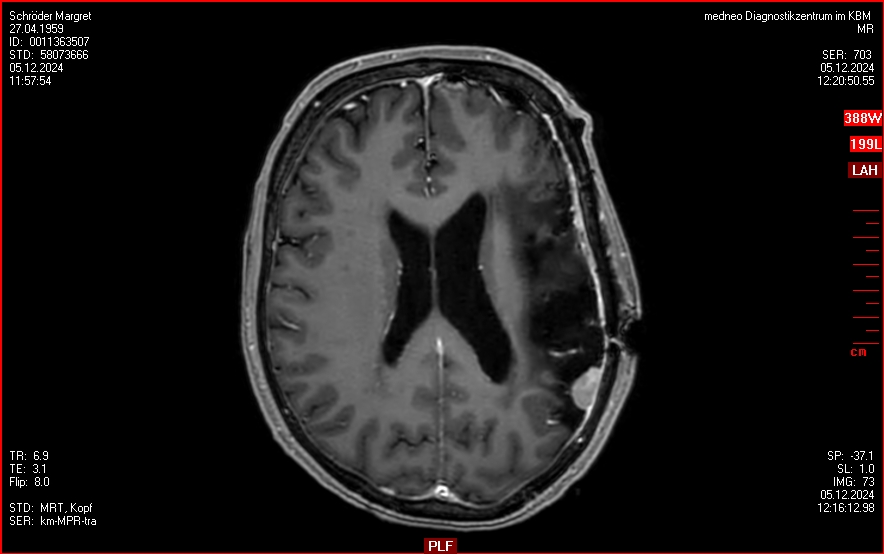

05.12.2024: MRT postoperativ

• komplette Resektion des links frontobasalen Meningeoms, des links frontoorbitalen Meningeoms sowie des  im Jahr 2021 im Gamma Knife behandelten Meningeoms. Die weiteren oben beschriebenen Meningeoms sind unverändert.